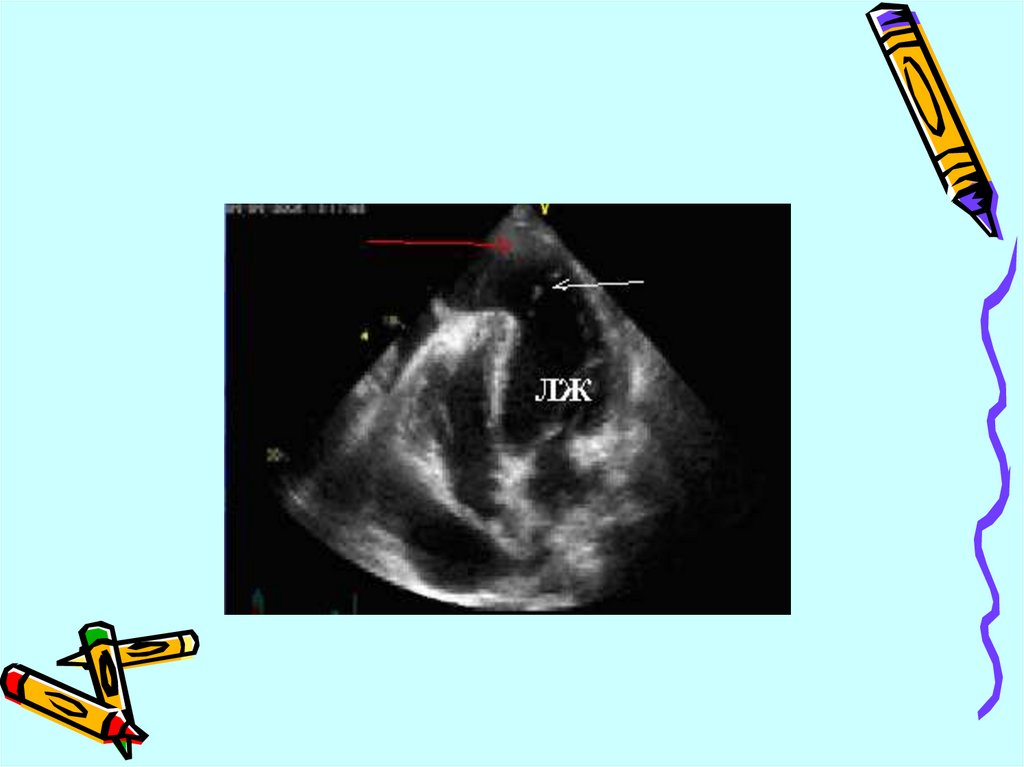

Тромбы в полости левого желудочка

Формирование аневризмы

Острая митральная регургитация

Дефект межжелудочковой перегородки

Эхокардиографические

особенности разрыва миокарда

• перикардиальная жидкость

• выраженные нарушения локальной

сократимости стенок

• в некоторых случаях объем

перикардиальной жидкости бывает

значительным и приводит к тампонаде

сердца (коллапс предсердий,

диастолический коллапс правого

желудочка)